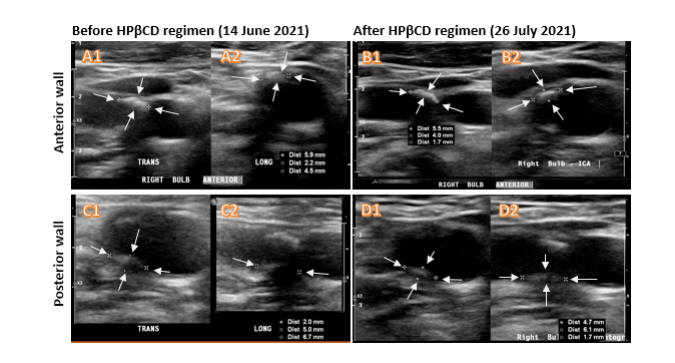

If you benefit from cyclodextrin, then thank Kyle Hodgetts. Kyle, a hypertensive, hyperlipidemic, long-standing smoker, by age 56, had required several rounds of stent placement. Standard medicine was not working. Kyle's physicians gave him little hope for future health. The adage "Necessity is the Mother of Invention" certainly applied here. Kyle had just lost his wife to illness. The couple had two young children. What would happen to them if Kyle died? Kyle, a researcher, read Dr. Zimmer's article (convincing animal model evidence that cyclodextrin will reverse atherosclerosis). I also read this article too, got excited, and soon after lost interest as cyclodextrin was then not available in the US. Kyle read the Zimmer study, and then every other paper he could find on this molecule (there is a lot - I've now read it all too). Kyle found a source of pharmaceutical grade CD, and then, assisted by his medical and scientific team, began to treat himself with IV cyclodextrin. Kyle and his medical group kept careful records and published the results. As depicted below, Kyle experience rapid (months, not years) coronary disease regression (documented by angiography), corroborated by carotid plaque regression (documented by ultrasound), and his lipid panel improved. Representative images are presented below. You can read the published reports yourself (Kyle's coronary angiogram, Kyle's' carotid ultrasound). Kyle tells his story, and discusses the science of cyclodextrin, on cholrem.com. You will note that everything Kyle says is pretty much everything that I am saying. I am not parroting Kyle, nor visa versa. We both studied the literature and came to the same scientific conclusions. The outcomes experienced by Kyle's clients are just what my patients are experiencing (as presented below). Cyclodextrin, once it is understood by all (a job I have assigned to myself) and put into widespread use, is going to save millions of lives, decrease the need for surgical interventions, and save billions of dollars. Kyle, in this regard, deserves a Noble Prize - he brought this to you!

Our patients are certainly benefiting from cyclodextrin, and as your will see below, we have documented carotid bulb soft plaque regression, but why would cyclodextrin affect CAC, which we view as an indicator of "hard plaque"? On the other hand, the mechanisms of vascular calcium build up are not well defined. We know that cyclodextrin will dissolve crystalline cholesterol as well as intracellular lipid droplet cholesterol.

These case studies suggest that we can use CT angiography. coronary artery calcium score reduction, or carotid plaque change, as non-invasive indicators of cyclodextrin efficacy, in patients with or without symptoms.